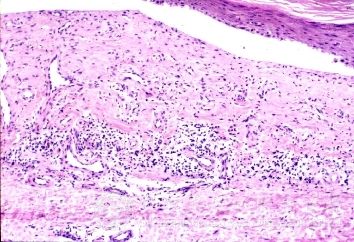

女性生殖器梅毒初期症状好发生于大小阴唇内侧部位,也可发生于子宫颈等处。同时双侧腹股沟淋巴结肿大,但不痛。通过接吻感染者,硬下疳可发生于唇、下颌部和舌等部位,也可发生于眼睑、手指和乳房等处,有时硬下疳未愈合前可同时伴发其他性病,如淋菌性皮炎。